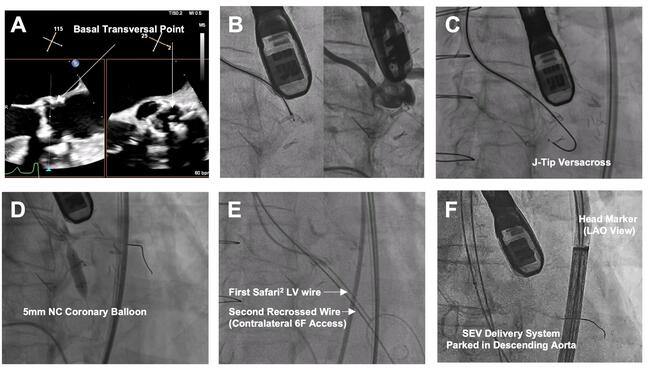

- Position a 7F guide (left: Amplatz Left 1/2; right: Multipurpose), 135-cm NaviCross catheter (Terumo), and 0.035-inch J-tip VersaCross wire (Boston Scientific) at the base of the target leaflet (Figure A and B). Traverse with radiofrequency (Figure C), cross the microcatheter, and exchange for a 300-cm coronary guidewire.

- Dilate fenestration with a 5-mm noncompliant coronary balloon (Figure D). Cross the microcatheter and exchange for a pre-shaped stiff wire. Recross the fenestration from contralateral 6F access with a second guidewire (0.035-inch straight-tip EMERALD [Cordis] or J-tip [Terumo]), using a similar 7F guide (Figure E). Exchange the second wire for an Amplatz Extra Stiff (Cook Medical).

- Deliver an Evolut FX+ valve (Medtronic) via primary access to the descending aorta, with the head marker oriented along the outer curvature under left anterior oblique projection to facilitate commissural alignment (Figure F).

- Dilate the fenestration with an 8-mm peripheral balloon via contralateral access (Figure G); this facilitates subsequent crossing of the SEV. The target leaflet is not lacerated at this stage.

- Position a 12-mm peripheral balloon and the SEV delivery capsule side by side across the fenestration. (Figure H). Gradually inflate the balloon until “give-way,” indicating leaflet laceration (Figure I). Deploy the SEV (Figure J) and simultaneously deflated balloon, and withdraw the guidewire. Controlled pacing may enhance stability. Near-simultaneous leaflet laceration and SEV deployment preserves hemodynamics; it also entraps the lacerated leaflet and places it away from the coronary ostium if the balloon pushes the SEV toward the annulus. (Figure-1K/1L)